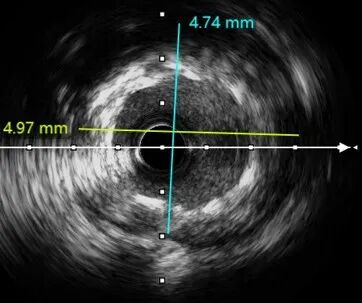

经后扩复查IVUS

LAD中远段支架贴壁良好,LAD开口显示有明显支架贴壁不良

LAD近端EEM直径4.74mm,送入4.5*15 NC进行后扩

PCI术后IVUS

IVUS提示:后扩张处理后支架膨胀、贴壁良好